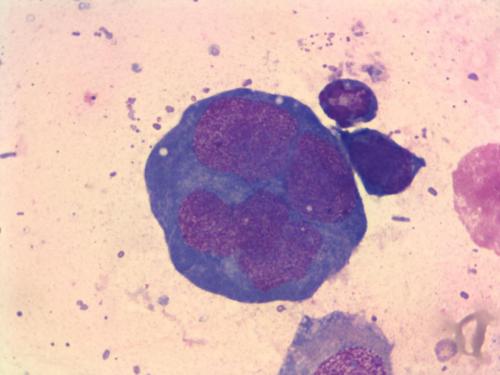

小淋巴细胞淋巴瘤(SLL)是一种非霍奇金淋巴瘤。它与慢性淋巴细胞白血病(CLL)相似和治疗方法也相似。

最常用的靶向治疗类型是称为利妥昔单抗的单克隆抗体。单克隆抗体治疗用于B细胞上的SLL靶蛋白。这使得B细胞死亡。